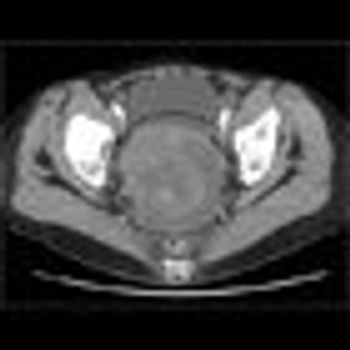

Challenge your diagnostic skills. What uterine-related findings are revealed in this pelvic scan?